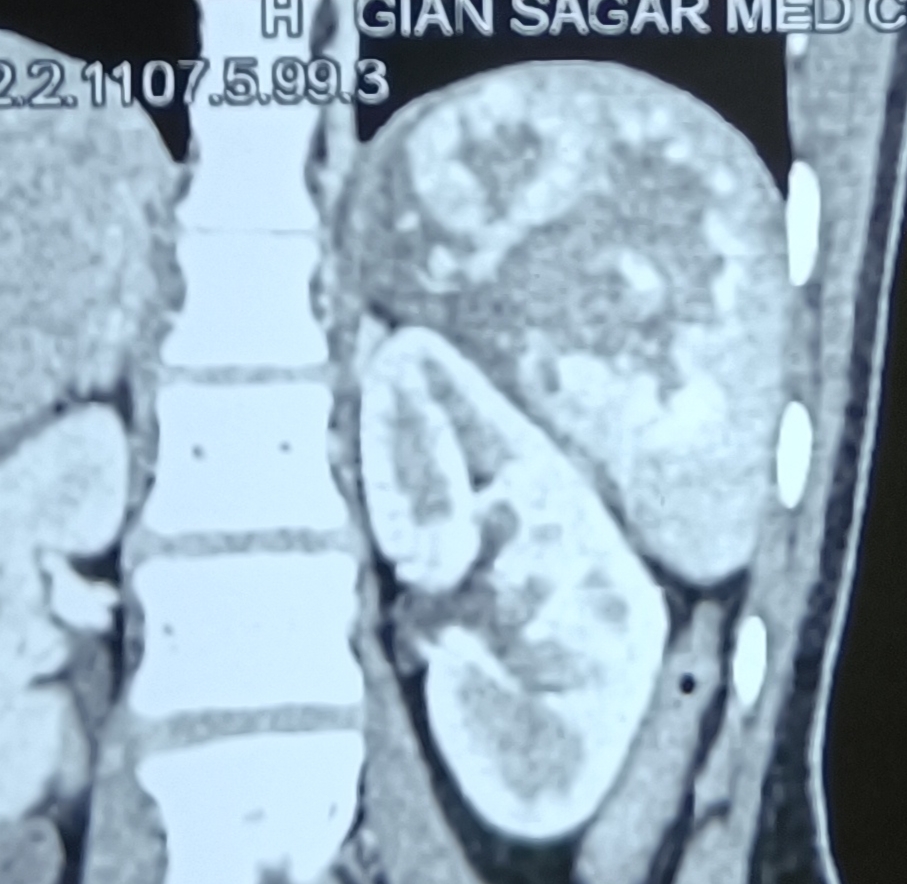

Big epididymal cyst/tumor. A hospital employee (in GSMCH), 35 years old, presented with a big scrotal swelling, diagnosed as hydrocele on ultrasound scan. At operation, there was scant amount of fluid around the testis, and instead, there was a big epididymal swelling, rather inseparable from the testis. Therefore, an epididymoorchidectomy was performed. Biopsy report later turned out to be an epididymal cyst, not hydrocele.